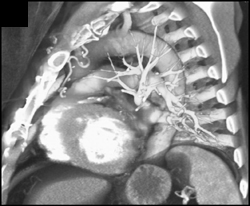

Small Descending Aorta